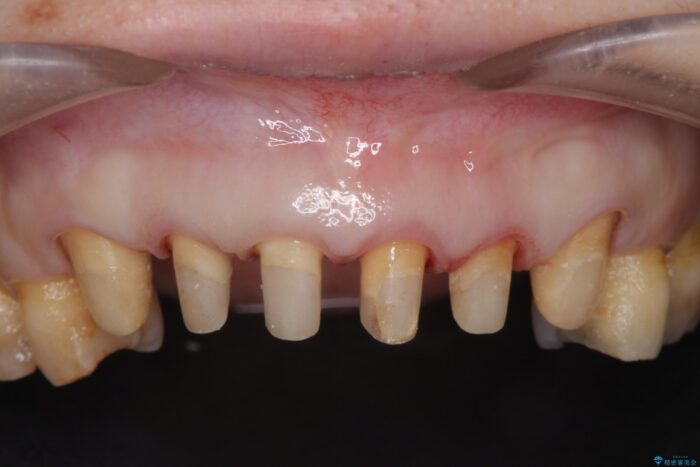

治療計画

装着されていたセラミックを除去したところ、歯ぐきの奥深くまで歯牙は削られ、歯ぐきの炎症・出血が著しくみられる状態でした。

この状態で再度セラミッククラウンの作製・装着を行ってもまた同じ状態となってしまうため、歯周外科を行い歯ぐきの状態を整備したのちセラミッククラウン治療をおこなっていきます。